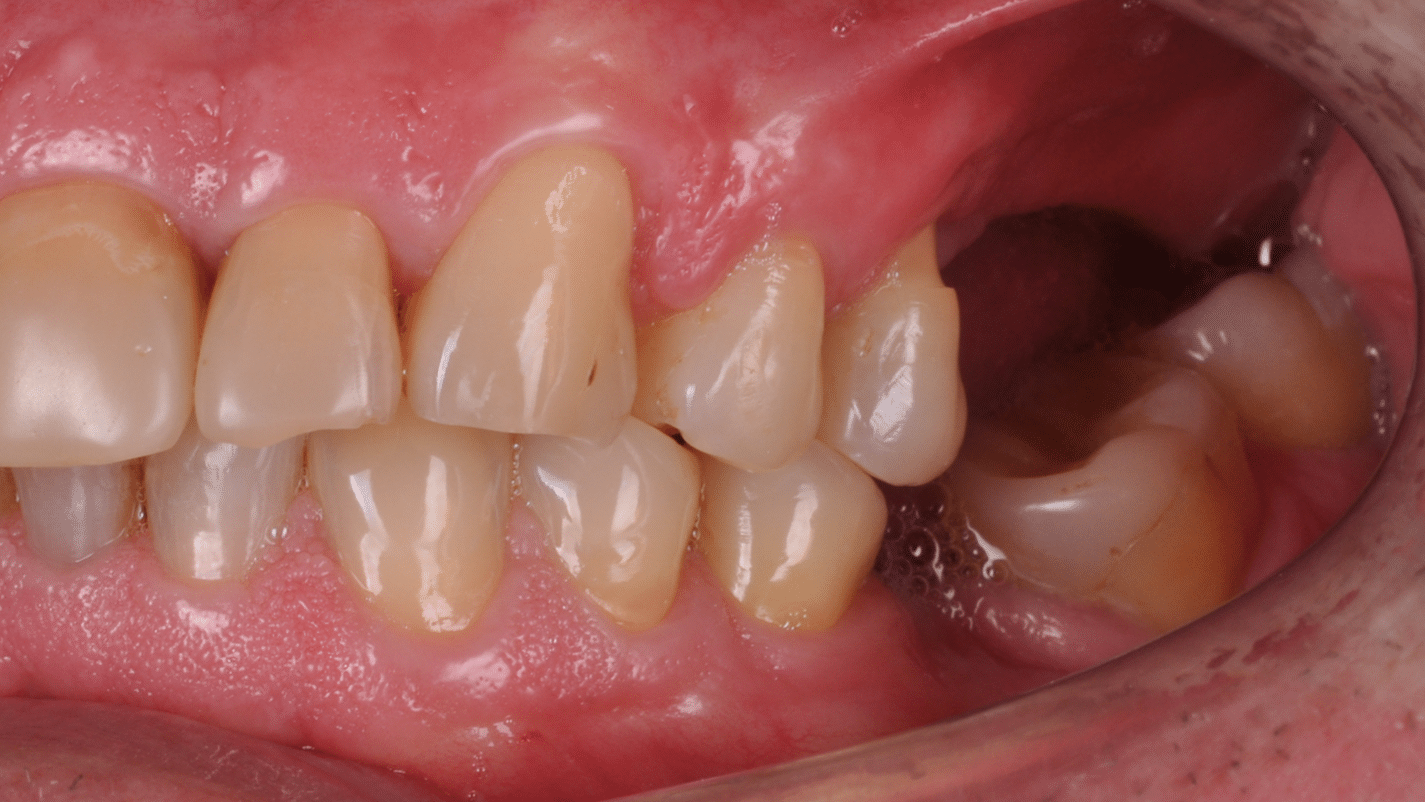

S-a planificat individual poziția și axul de inserție al fiecărui implant.

Doar astfel putem crea profilul de emergență corect al coroanei dentare, ceea ce permite conformarea papilei și a sulcusului.